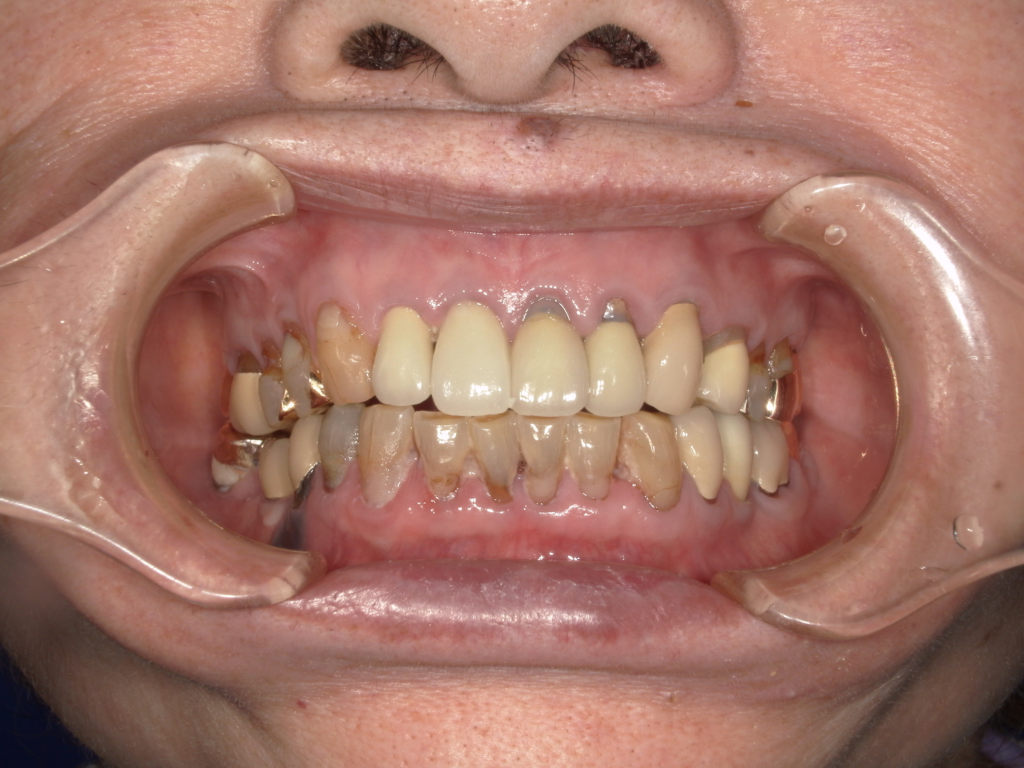

上の前歯4本をインプラント治療で治しています。前歯4本を抜歯して、真ん中の歯に2本インプラントを埋入しています。抜歯したと同時に仮歯(前歯4本)を作りました。最終な上部構造物は、セラミックスで仕上げています

治療前

治療後